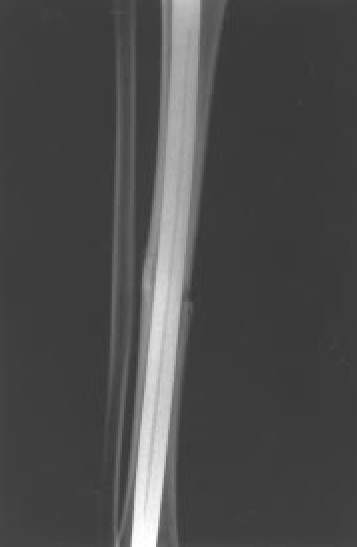

Fig. 9B.: Control radiológico mostrando resolución de la fractura con un clavo intramedular AO.